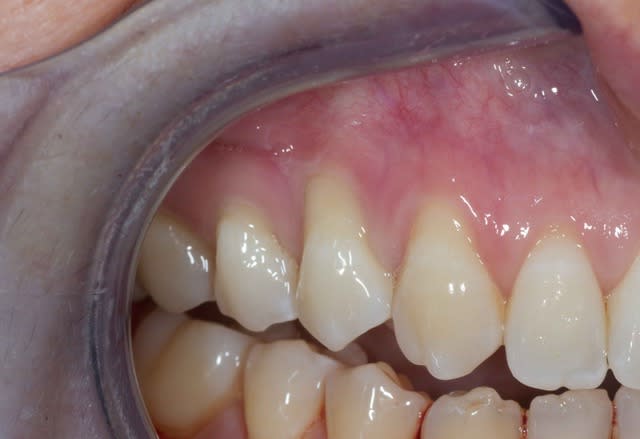

Pour boucler un fils commencé un peu plus haut voila la cicat.

Tunnel+ conjonctif tracté

Joli cas.

Mais si je peux me permettre le recouvrement est incomplet même si récession était assez importante sur la 14 .

Il est dommage de ne pas avoir englober le récession débutante sur la 12.

Je n'aurais pas osé dans ce cas faire cette technique et aurait préféré une greffe de gencive libre puis un LTC, certes moins esthétique et plus longue mais plus pérenne AMHA en regard de la 14.

toutefois je ne connais pas le désir du patient et je trouve le résultat assez satisfaisant.

Tu as mis un conjonctif ou du mucograft?